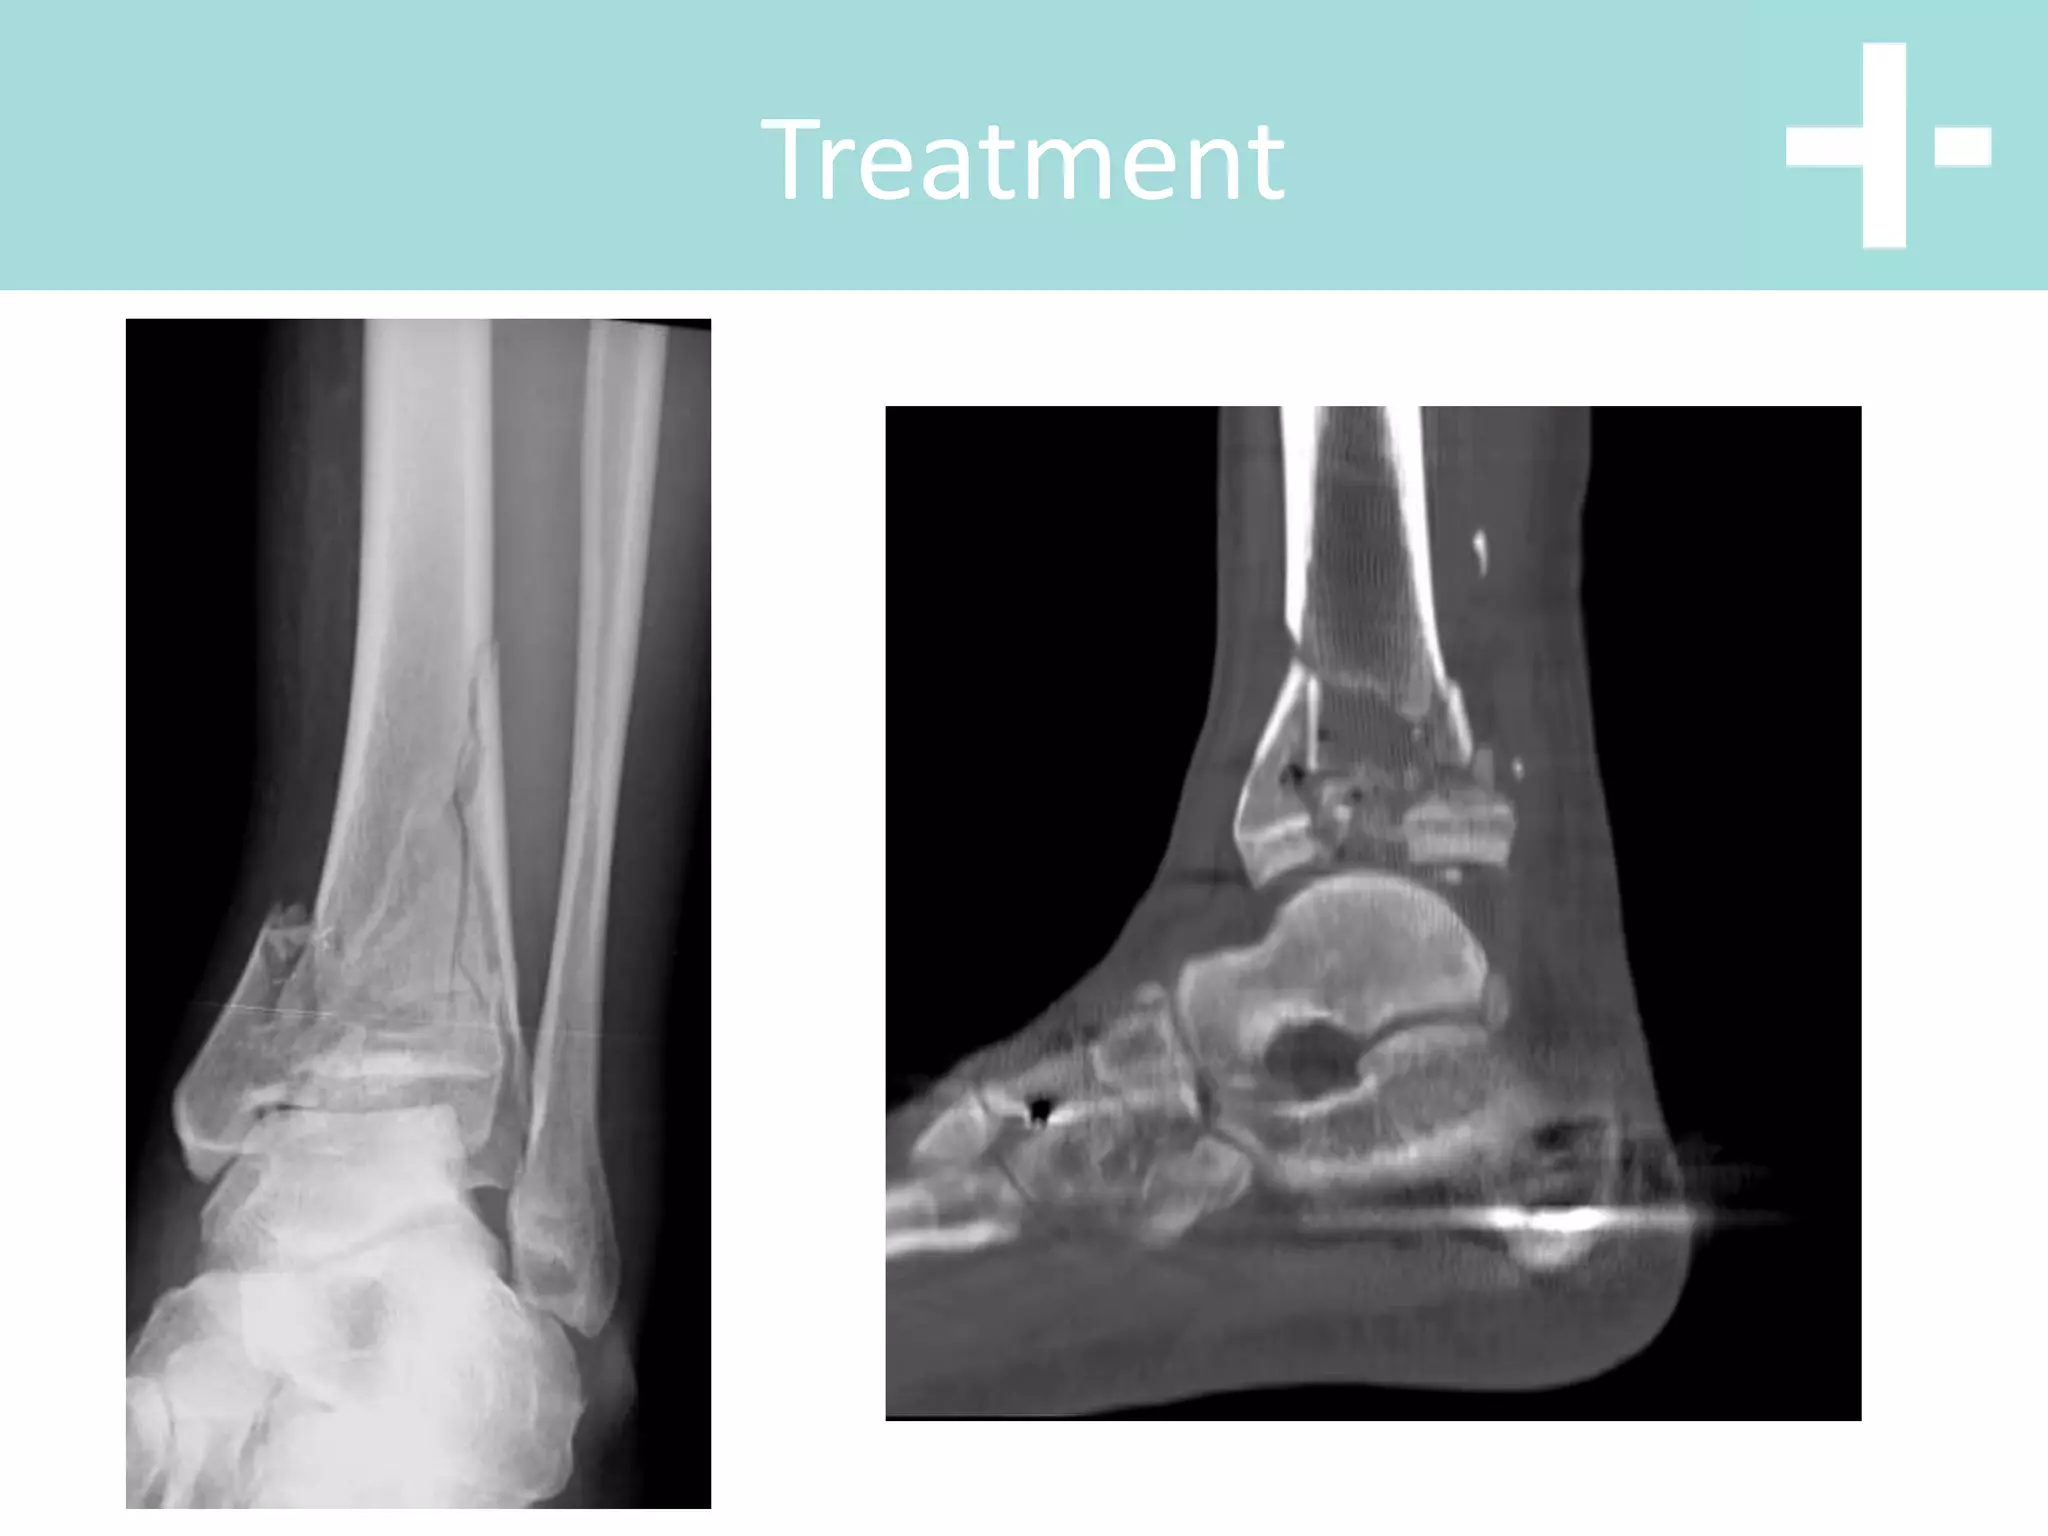

Treatment

• Safe to apply temporising

spanning ex-fix

• Leave until swelling

resolved approx 14 days

• Investigate with CT